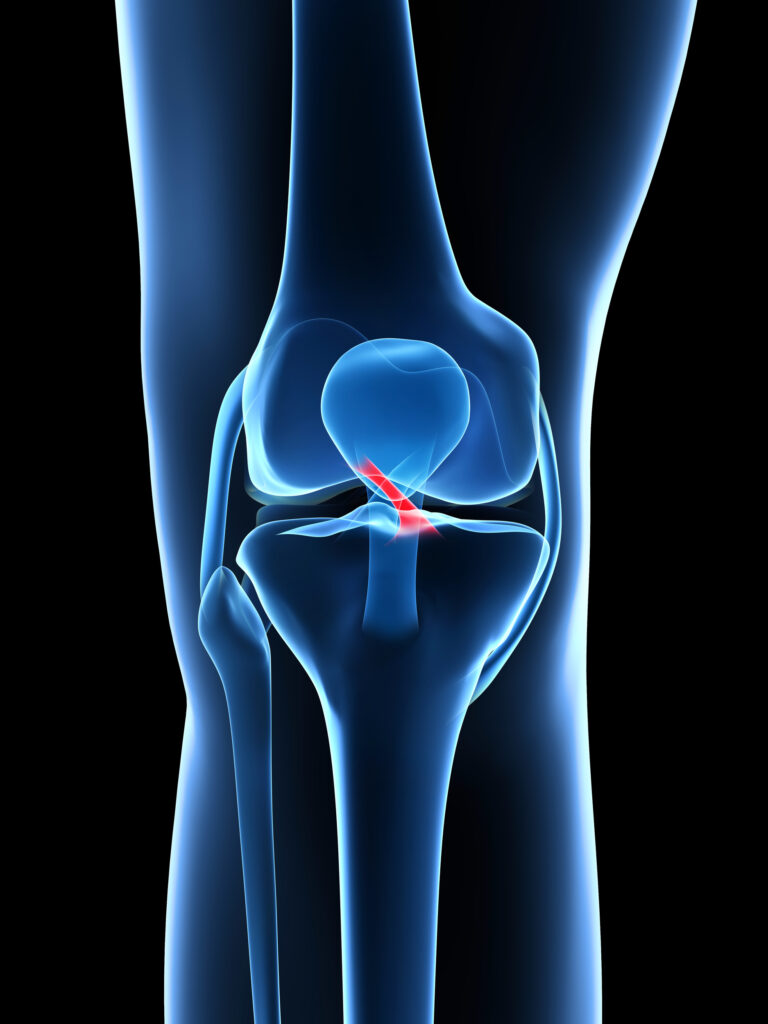

Ce este ligamentul încrucișat anterior?

Ligamentul încrucișat anterior (LIA) este unul dintre cele patru ligamente principale ale genunchiului, situat în centrul articulației. El leagă femurul de tibie și are rolul de a controla mișcările de rotație și de a împiedica deplasarea anterioară a tibiei față de femur.

Împreună cu ligamentul încrucișat posterior, LIA asigură stabilitatea genunchiului în activitățile dinamice precum alergarea, săriturile și schimbările bruște de direcție.